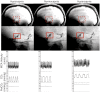

The larger intracranial conduit vessels contribute to the total cerebral vascular resistance, and understanding their vasoreactivity to physiological stimuli is required when attempting to understand regional brain perfusion. Reactivity of the larger cerebral conduit arteries remains understudied due to a need for improved imaging methods to simultaneously assess these vessels in a single stimulus. We characterized reactivity of basal intracranial conduit arteries (basilar, right and left posterior, middle and anterior cerebral arteries) and the right and left internal carotid arteries, to manipulations in end-tidal CO2 (PetCO2). Cross-sectional area changes (%CSA) were evaluated from high-resolution (0.5 mm isotropic) images collected at 7 T using a T1-weighted 3D SPACE pulse sequence, providing high contrast between vessel lumen and surrounding tissue. Cerebrovascular reactivity was calculated as %CSA/ΔPetCO2 in eight healthy individuals (18-23 years) during normocapnia (41 ± 4 mmHg), hypercapnia (48 ± 4 mmHg; breathing 5% CO2, balance oxygen), and hypocapnia (31 ± 8 mmHg; via hyperventilation). Reactivity to hypercapnia ranged from 0.8%/mmHg in the right internal carotid artery to 2.7%/mmHg in the left anterior cerebral artery. During hypocapnia, vasoconstriction ranged from 0.9%/mmHg in the basilar artery to 2.6%/mmHg in the right posterior cerebral artery. Heterogeneous cerebrovascular reactivity to hypercapnia and hypocapnia was characterized across basal intracranial conduit and internal carotid arteries.